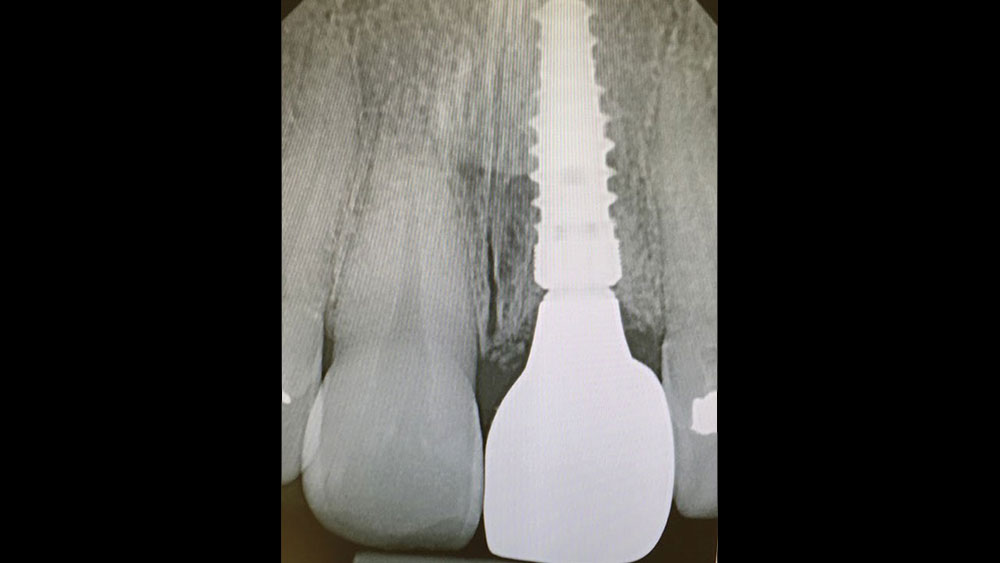

Following well-established clinical research methods, bone loss was measured as the distance from the implant shoulder to the first contact of bone to implant, from both the mesial and distal sides.

Figures 1a, 1b: Calibration of the bone loss measurements was determined by measuring the length of the implant (1a), or by measuring the diameter in cases where the implant apex was not visible (1b).